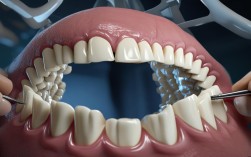

修复体设计:

(图片来源网络,侵删)- 牙冠外形: 仿生化的牙冠外形(邻接点、舌侧形态)有利于自洁和健康牙龈的维持。

- 咬合关系: 咬合创伤会导致牙龈退缩和骨吸收。